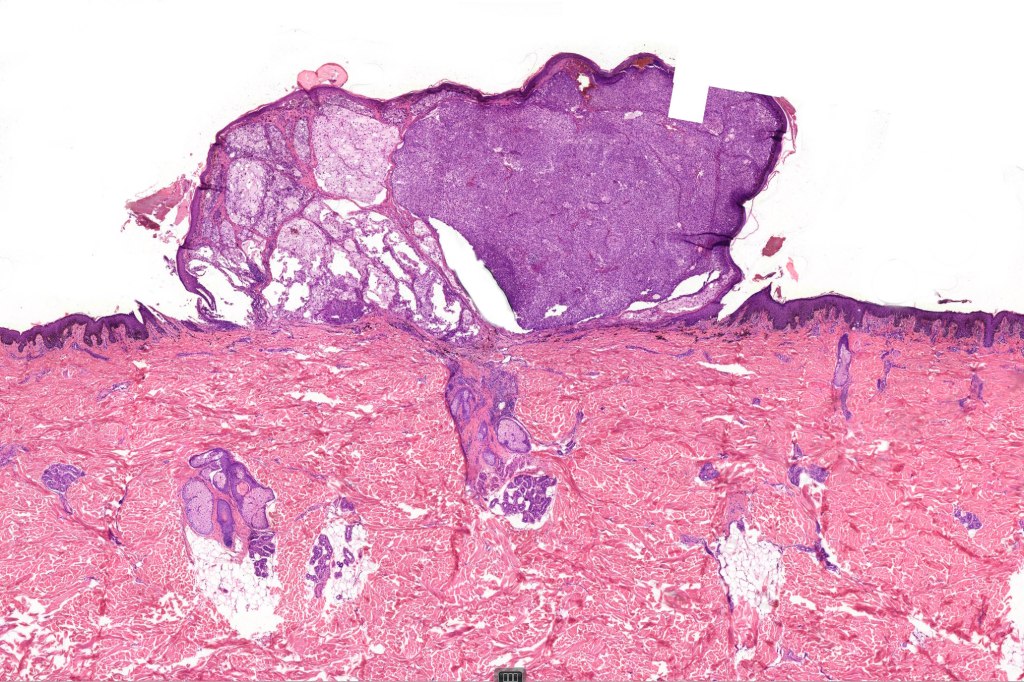

•Very rare variant of melanoma

•Back> lower & upper extremities> head & neck> choroid

•Often ulcerated nodules

•Poor prognosis is likely related to large tumor size at presentation

•May affect the tumor in part or whole